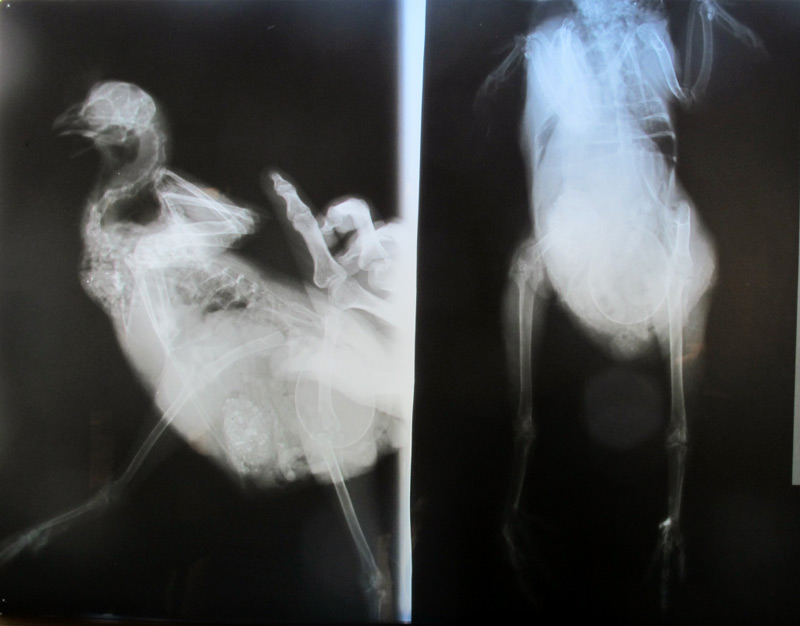

Ist der Ruf erst ruiniert, lebt es sich ganz ungeniert. 8) Immerhin ist nichts gebrochen.Gluckengrüße ;)

Dateianhänge

greta_durchleuchtet.jpg

Das Ei sieht man schon :D.

Ja und den gefüllten Kropf mit Körnern und Muschelgrit sieht man auch. :) Weil die Kleine so tapfer war habe ich der Bande danach Blaubeeren gekauft. ::)

Das wissen wir jetzt leider immer noch nicht. Die Bänder kann man bei der Röntgenaufnahme nicht sehen. :-\ Heiserer Hahn klingt aber auch echt gut. ;D Was hatte er denn?

Greta durchleuchtet

das sieht ja irre aus ;D. war sie eigentlich schwer zu halten?

Im Film kann man das Gehumpel von Greta deutlich sehen. :-\ Gut, daß nichts gebrochen ist.

Abgesehen vom Humpeln macht Greta einen guten Eindruck, so weit ich das beurteilen kann.Liebe späte GrüßeThomas